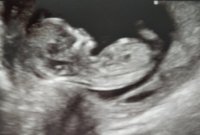

Jos ei pääse neuvolan kautta tarkistamaan, ettei ole keskeytyny, niin sitten pitää kyllä varmaan jo maksella yksityiselle ultra.